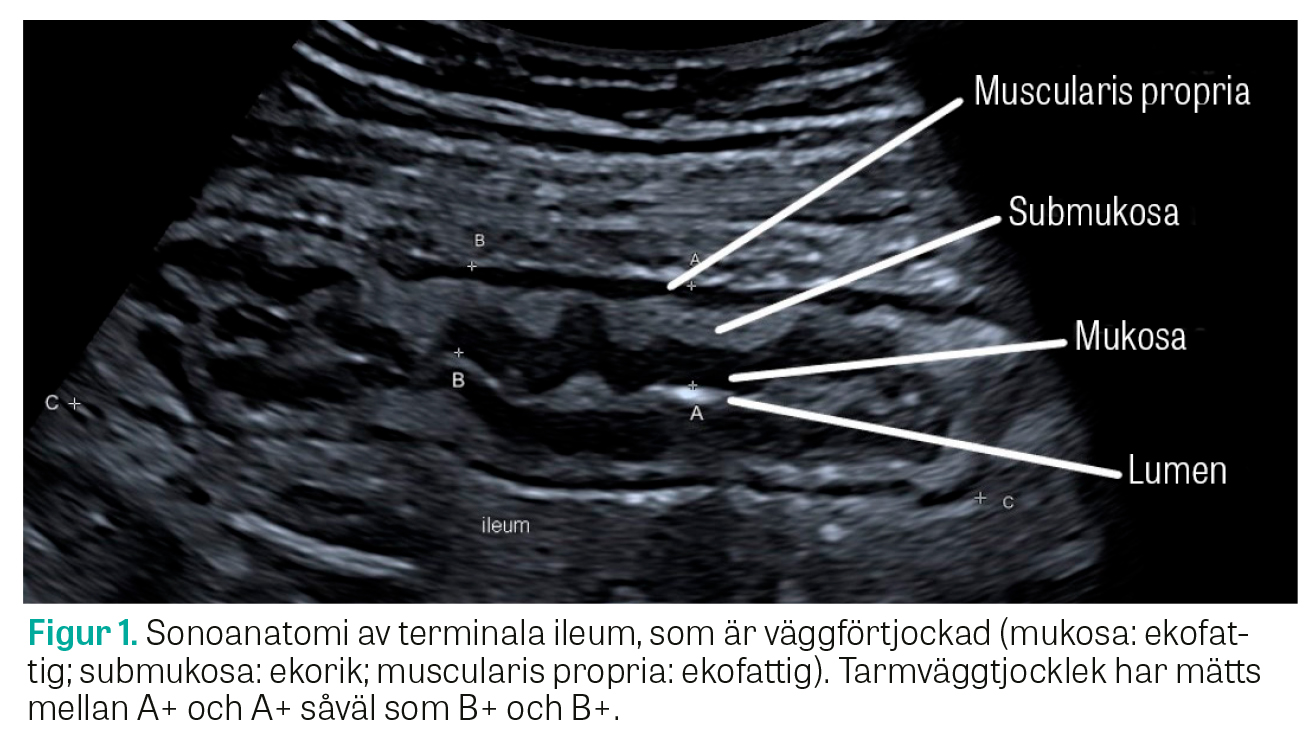

Efter översiktlig undersökning med den konvexa givaren fortsätter man undersökningen med den linjära givaren för en mer detaljerad bild samt mätning av tarmväggtjockleken (eng: bowel wall thickness, BWT) (se Figur 1 för sonoanatomi och Figur 2 för normalfynd i terminala ileum). Andra parametrar som bedöms är tarmväggsvaskulariteten, huruvida tarmväggskiktningen är välavgränsad eller utsuddad som tecken på inflammation, om det föreligger inflammation i det omkringliggande mesenteriella fettet och om det finns förstorade lymfkörtlar (se Figur 3 för ökad tarmväggtjocklek, vaskularitet och inflammatoriskt fett). Tjocktarmssegmenten undersöks systematiskt, sedan terminala ileum och hela tunntarmspaketet [16, 18].

Det mått som med högst grad av känslighet och reproducerbarhet avspeglar aktiv inflammation är tarmväggens tjocklek. En väggtjocklek upp till 3 mm anses normal, medan >3 mm indikerar att tarmväggen är inflammerad.